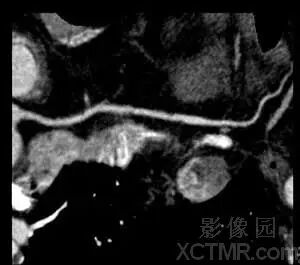

最大密度投影(MIP)

MIP是利用容积数据中在视线方向上密度最大的全部像元值成像的投影技术之一。因为成像数据源自三维容积数据,因而可以随意改变投影的方向;因为成像数据取自三维容积数据中密度最大的像元值,因而其主要的优势是可以较真实地反映组织的密度差异,清晰确切地显示经对比剂强化的血管形态、走行、异常改变和血管壁的钙化以及分布范围,对长骨、短骨、扁骨等的正常动态和骨折、肿瘤、骨质疏松等病变造成的骨质密度的改变也非常敏感。此外,对体内异常的高密度异物的显示和定位也具有特别的作用。由于以上特点,MIP作为一种有效的常规三维图像后处理技术广泛地用于显示血管、骨骼和软组织肿瘤等病变。MIP的缺点是对密度接近且结构相互重叠的复杂解剖部位不能获得有价值的图像;图像缺乏空间深度感,难以显示颅内走行复杂的动、静脉血管之间和与颅骨之间的三维空间关系。克服上述缺点的主要方法是用Clipping、Cutting、Seed或Segmentation等技术去除靶器官以外的组织影像的干扰和对图像进行适当角度的旋转。

MIP比VR显示髂动脉钙化更加清晰。